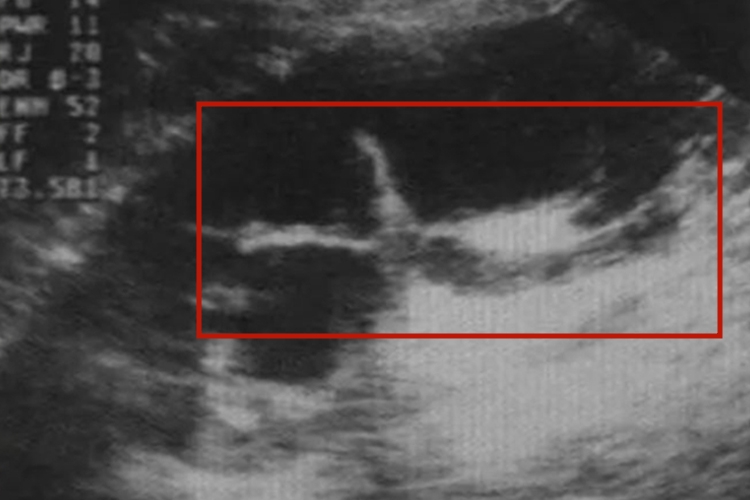

病理性肾盂分离声像图上高回声的肾窦内出现无回声区,肾窦分离扩张,分离大于1.5m,可能伴有肾盏扩张。扩张的肾盏间互相连接,肾皮质明显变薄,甚至菲薄呈线状。